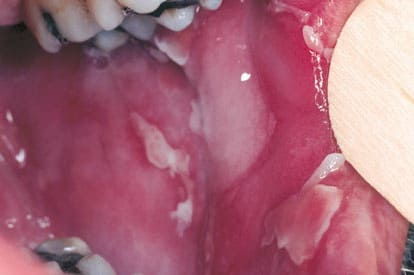

Pemphigis Vulgaris =الفقاع الشائع